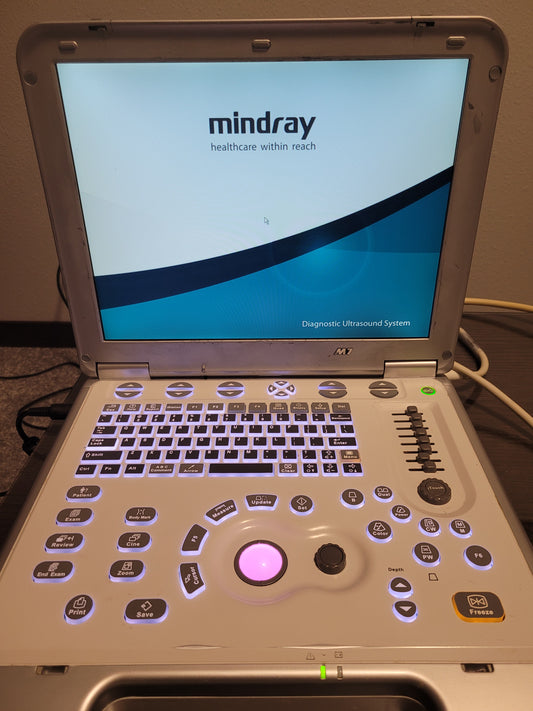

Mindray M7 Ultrasound with Probe

Regular price $6,500.00 USDRegular priceUnit price / per -